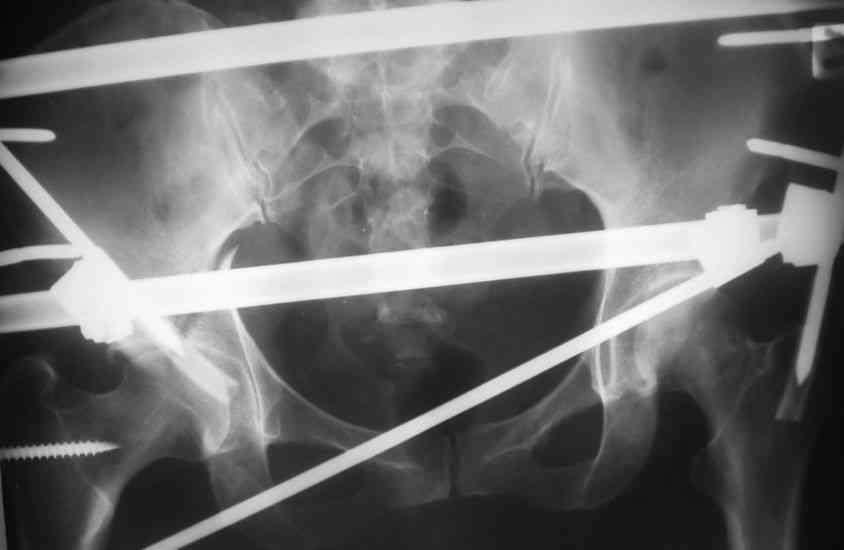

Пациентка 38 лет. В результате ДТП 02.09.06 получила поперечный перелом правой вертлужной впадины, центральный вывих правого бедра, разрыв правого крестцово-подвздошного сустава.

В одной из районных больниц вывих устранен, наложена система вытяжения по оси бедра и за вертельную область. Спустя 2 недели выполнен ВЧКО модулем "таз-бедро". Учитывая возраст пациентки и остаточный диастаз в области свода вертлужной впадины предполагается демонтаж аппарата, открытая репозиция и внутренний МОС вертлужной впадины через внутритазовый доступ.

На показанных снимках повреждение правого КПС не очень заметно...

У меня создалось впечатление( одна из РГ), что участок суставной поверхности нагрузочной зоны вертлужной впадины вдавлен( постарайтесь сделать КТ). Если это подтвердиться, то из внутритазового доступа отрепонировать будет невозможно.

Чтобы уменьшить риск инфекции после открытой репозиции перед основным вмешательством неплохо было бы дождаться полного заживления стержневых

проколов.